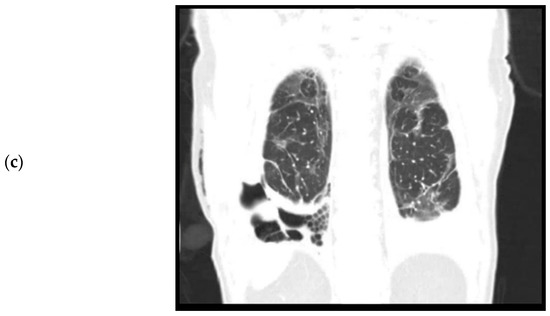

Figure 1.

Computed tomography, coronal plane. (a). April 2020. Level of trachea bifurcation. Bilateral consolidations and ground glass opacities during active SARS-CoV-2 infection. (b). September 2020. Level of trachea bifurcation. Bilateral residual ground glass opacities. (c). September 2020. Level of thoracic vertebrae. Right sided loculated pleural effusion, pleural empyema, and trapped lung.

During admission, the patient did not have a fever. Oxygen saturation was 97% with 6 L oxygen. Laboratory results showed a white count of 16.6 × 109/L (reference: 4.0–10.0 × 109/L) and a C reactive protein (CRP) of 139 (reference < 5.0). Chest X-ray and chest CT performed on the day of admission showed bilateral consolidations and ground glass opacities without pleural effusion, suspicious for a COVID-19 infection (Figure 1a). Furthermore, pleural plaques were present on the right and left hemidiaphragm without evidence of round atelectasis or focal ischemia of the lung parenchyma. Multiple Polymerase Chain Reaction (PCR) for SARS-CoV-2 from nasopharyngeal swabs were negative, but after a few days a SARS-CoV-2 rectal swab was positive. This test was never repeated. The patient was admitted for oxygen support through a nasal cannula and cefuroxime and azithromycin were administered to prevent a bacterial superinfection. Furthermore, prophylactic low molecular weight heparin (nadroparine, 2850IE once daily) was started. The patient did not require mechanical ventilation. On the eleventh day of admission, a CT angiography of the chest was performed because of ongoing oxygen support. This showed a decrease in consolidations, but new bilateral segmental pulmonary embolisms, for which dabigatran was initiated. No coagulation parameters were tested during the admission. The patient could be weaned off oxygen support and after two weeks of admission, was discharged to a nursing home for further recovery. From there, eventually patient was discharged home in good condition.

The patient was re-admitted for observation. Laboratory results showed a white count of 10.7 × 109/L and a CRP of 79. A culture of the pleural fluid was negative for bacteria. A chest CT performed after drainage showed bilateral residual ground glass opacities after the initial COVID-19 infection (Figure 1b) and a right-sided loculated pleural effusion (Figure 1c), suspicious for a thoracic empyema. The patient was referred to our hospital, a tertiary care center for thoracic surgery, for pleural decortication.